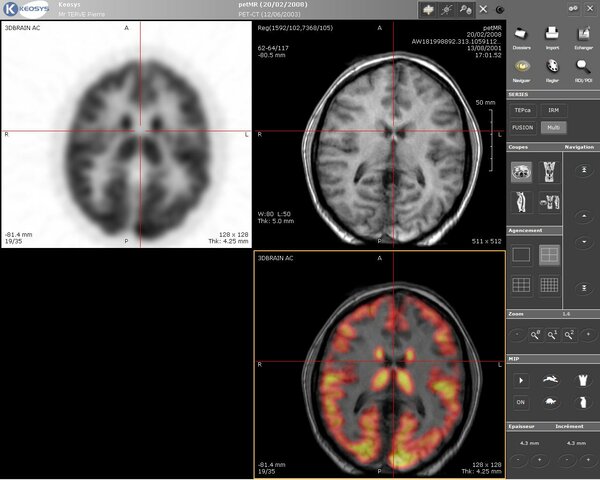

• IMAGENES DE IRM

Edelstin consigue obtener imágenes de IRM del cuerpo humano utilizando el método propuesto por Ernst